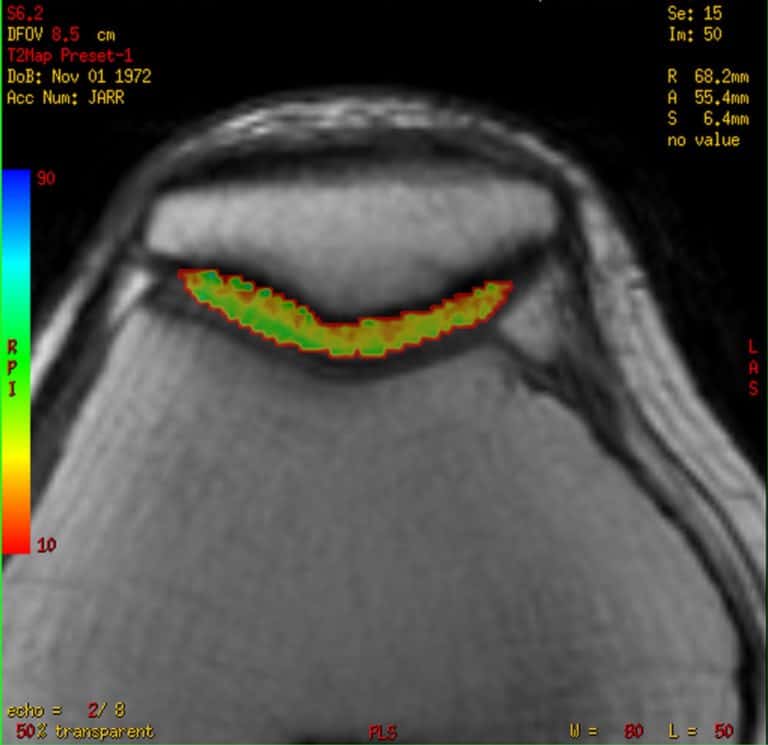

Es un estudio especializado de resonancia magnética donde se aplican secuencias específicas para la valoración del cartílago articular y detectar lesiones iniciales, aun cuando no son visibles en las secuencias convencionales. Esto se logra mediante secuencias que se conocen como mapa T2 o cartigram que consiste en la adquisición de un tren de ecos que permite el estudio del colágeno y la matriz extracelular del cartílago y así detectar lesiones microscópicas, permitiendo el diagnóstico y tratamiento tempranos, permitiendo a su vez realiza estudios de seguimiento para valoración de la respuesta del tratamiento inicial.